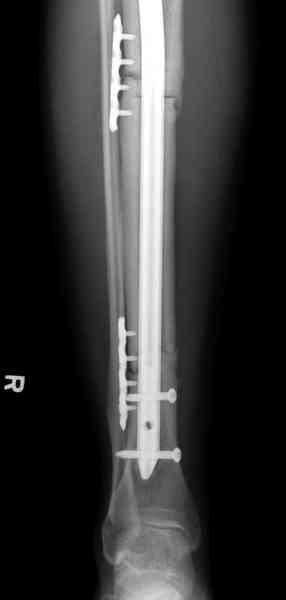

Жесткая Фиксация по три шурупа на сегменте удержат нагрузку на конечность.

Не оригинальное, подход не раз был демонстрирован нас в стране проф. Анатолием Федоровичем Лазаревым (ЦИТО), который это называет "металлокаркасная пластика". У нас в институте в другом отделении он

помогал сделать несколько таких металлокаркасов, только, насколько я помню, без блокируемых стержней. А в мире эта методика довольно давно

применяется, хотя и не массово. Например, осенью прошлого года на конференции общества Кюнчера в Страсбурге было хорошее сообщение на эту тему. 17 больных, результаты уже до 5 лет.

The cages are commercially available but up to 10 cm. So we measured the needed length on x-rays, added 2 cm at both ends for sure that

the resected piece will include all, and resulted with 15 cm which one was ordered and individually made by the same factory. So yes, we made the gap to fit the cage.

The inner diameter of the tube is 13 mm, the nail was 12 mm, so not so much space to put something inside. Yes, this is really shaft endoprosthesis which i hardly ever would offer for a young football player. Though... Maybe we would when we collect some experience with this sort of implants to feel/prognose its strength in different settings.